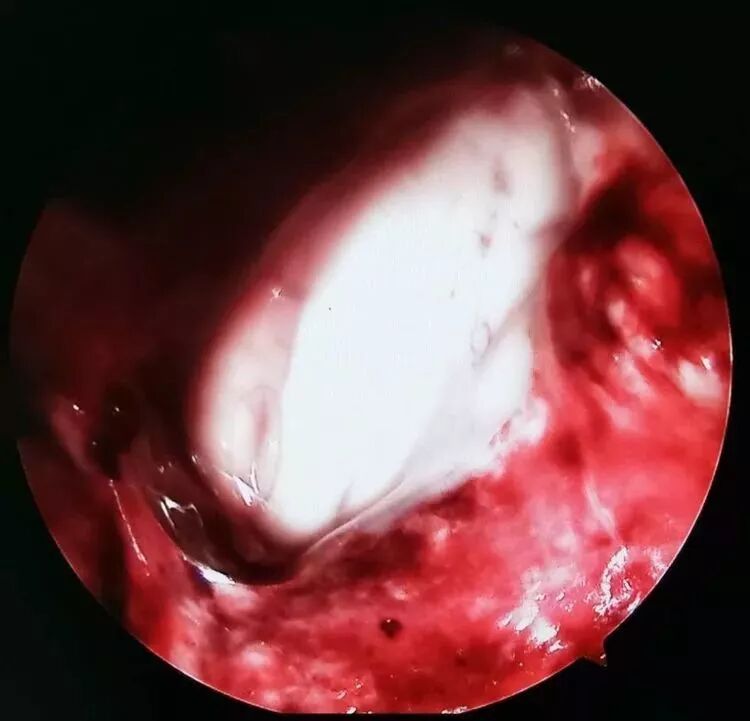

IV脑室内积血冲洗干净,可见IV脑室底诸结构。

骨孔直径2.5cm(图3白色圈为骨孔范围),皮层通道直径1.5cm(图3黄色圈为皮层通道直径)。